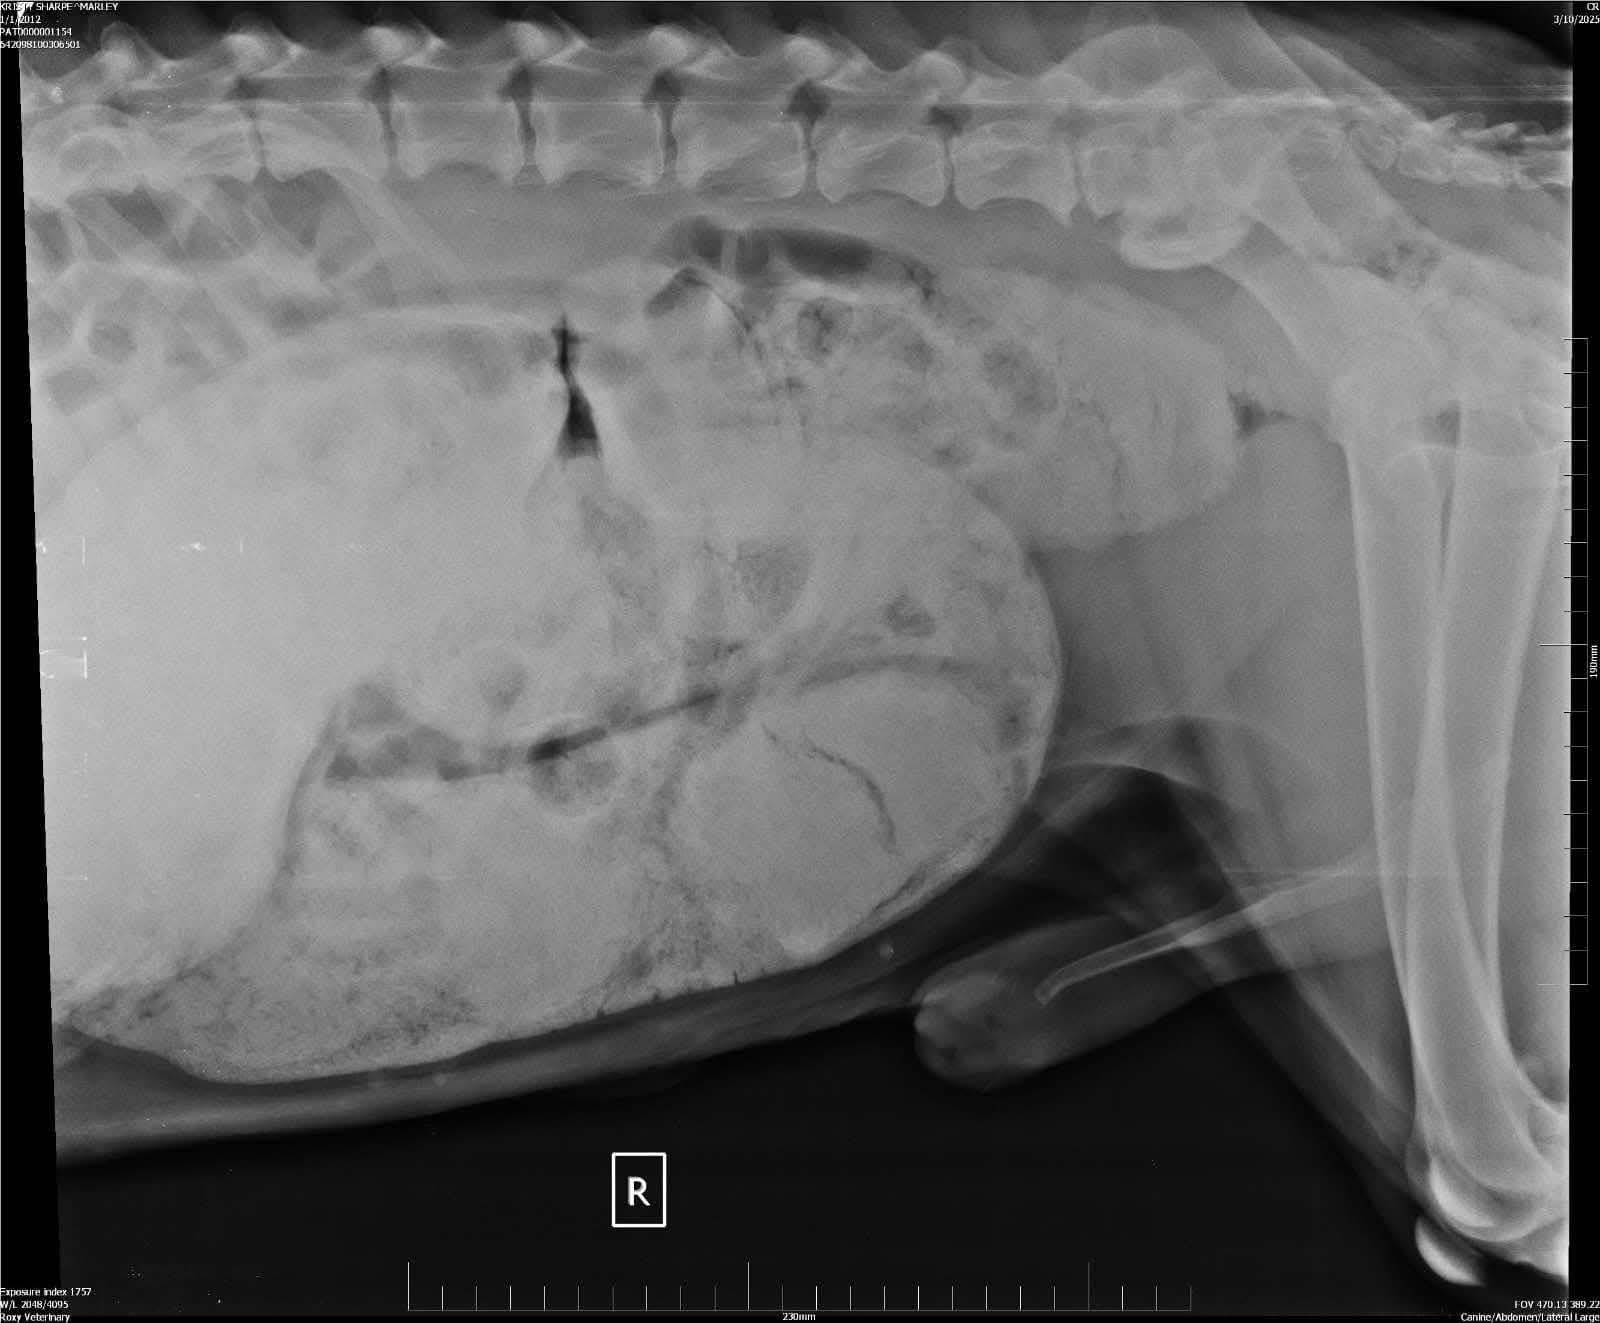

Our beautiful soul Marley took very unwell in March. It turned out he had a compacted bowel so bad that that it also resulted in three holes on his bowel.

Marley had life saving operation as well as other urgent health concerns taken care off. He was neutered as his prostate was enlarged which we think caused the bowel obstruction.